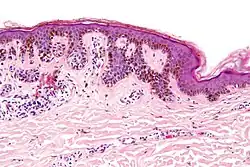

| Compound nevus | Both the epidermis and dermis.[17] |

|

ICD10: D22 (ILDS D22.L14) ICDO: 8760/0 | |